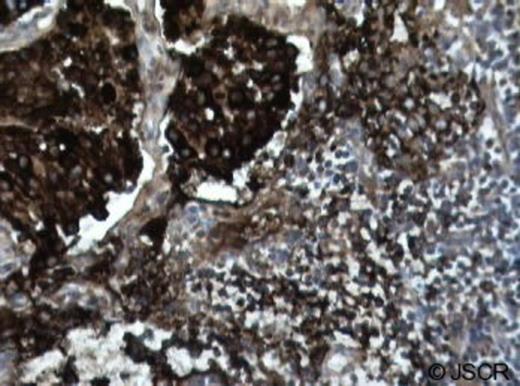

Prior to surgery, the patient had an interventional radiology tumour embolization. This was done to devascularize the tumour as thoroughly and safely as possible in order to limit the amount of surgical blood loss. The next day, the patient underwent a right neck dissection, parotidectomy and right glomus vagale tumour resection and right injection laryngoplasty. There were no peri-operative complications. The right vagus nerve, glomus vagale tumour, and right thyroid were sent to pathology. The dissected tumour mass can be seen in Figure 2. Surgical pathology confirmed the diagnosis of the neck mass as a vagale paraganglioma. The pathology report also revealed the presence of metastatic tumour in a positive chromogranin-stained lymph node, thus fulfilling the criteria for malignancy.

Chromogranin-stain of the dissected lymph node. Lymph node stained positive for chromogranin, confirming the presence of metastatic disease (dark brown/black cells).